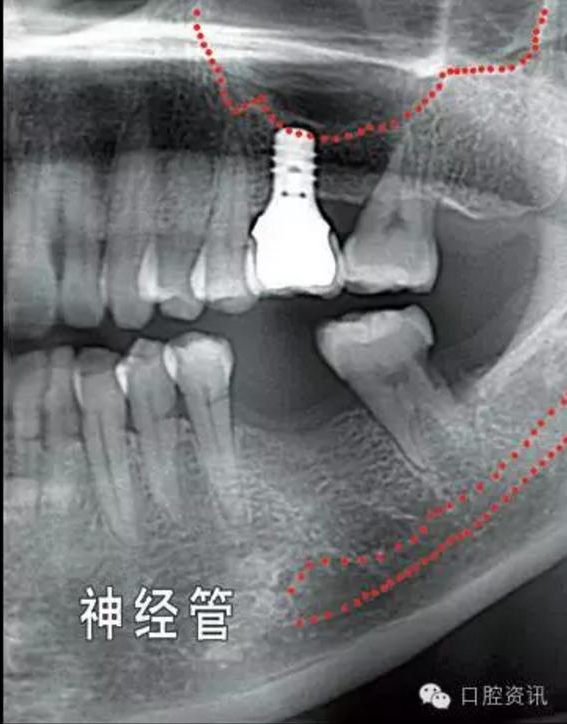

就種植手術(shù)本身而言,您頜面部一些重要結(jié)構(gòu)(例如下頜神經(jīng),上頜

竇) 的位置和形態(tài)會增加手術(shù)風(fēng)險和操作難度,為避免因手術(shù)損傷這

些重要結(jié)構(gòu),我們要求您手術(shù)前拍攝X光片作為參考,以便牙醫(yī)結(jié)合這些材料和您具體分析手術(shù)的風(fēng)險程度。

圖10. 可能影響種植牙手術(shù)操作的解剖結(jié)構(gòu)